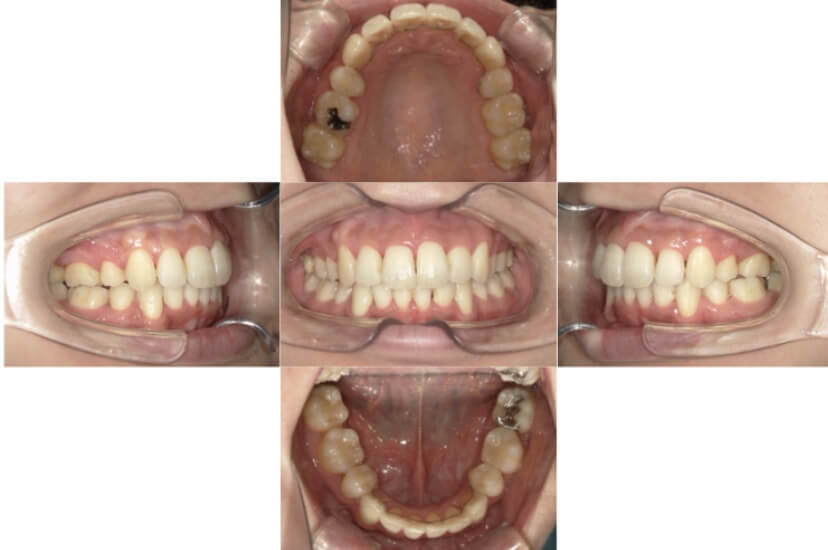

BEFORE

AFTER

症例4

下顎前突、叢生

抜歯

ブラケット矯正

上下顎叢生、反対咬合(上下の前歯のガタガタ、若干受け口)のケースです。

装置はラビアル(上下表側)で、上下顎の小臼歯を4本抜歯を行っています。抜歯したスペースを使って、上下の叢生改善と前歯の受け口の改善を行っています。

主訴 前歯のガタガタを治したい。

年齢・性別 45歳 女性

お住まいの地域 神奈川県川崎市

治療方針 抜歯スペースを利用して上前歯の叢生(ガタガタ)の改善と受け口の改善

抜歯部位 上顎左右第一小臼歯、下顎左右第二小臼歯

使用装置 ラビアル(上下表側)、顎間ゴム

治療期間 2年6か月

治療回数 20回

リテーナー クリアリテーナー